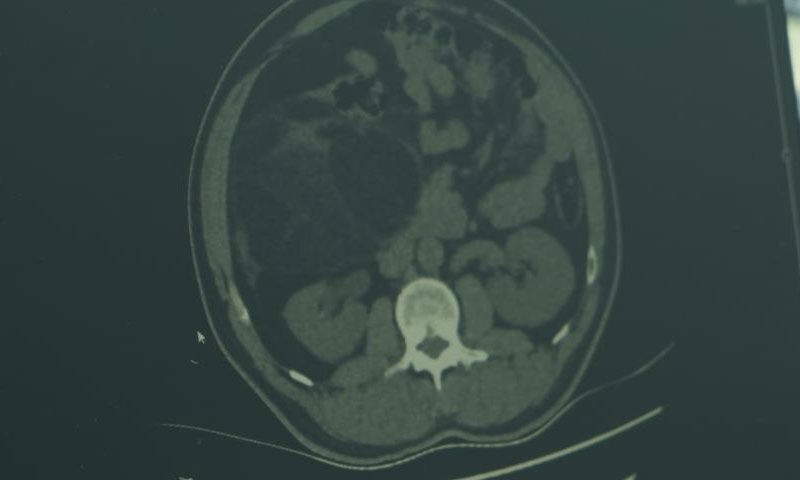

Hastaneye karın ağrısı şikâyetiyle başvuran 43 yaşındaki Özkan Ünal'ın yapılan tetkikler sonucunda, karın içinde yaklaşık 30 santimetre büyüklüğünde bir kitle tespit edildi. Pankreas, karaciğer ve böbrekle ilişkili bölgede yer alan dev kitle, yapılan operasyonla çıkarıldı.

Ameliyatı yapan Genel Cerrahi Uzmanı Opr. Dr. Volkan Kınaş, "Özkan Bey, hastanemize karında ağrı şikayetiyle geldi. Üroloji bölümüne başvurdu. Burada yapılan değerlendirmelerde hastanın karın içerisinde yaklaşık 30 santimetrelik bir kitle olduğu gözlemlendi. Bu kitle pankreas, karaciğer, böbrekle tamamen ilişkiliydi. Tabii, zor ve itina gerektiren bir ameliyattı. Bu tür vakalar çok nadir görülen, çok sık karşılaşmadığımız vakalardır. Gözden kaçırılmaması gereken ve ameliyatının titizlikle yapılması gereken vakalardır. Tüm hastalarımızda olduğu gibi kanser cerrahisinde de erken teşhisin önemi ve rolünden her zaman bahsetmek gerekir” dedi.